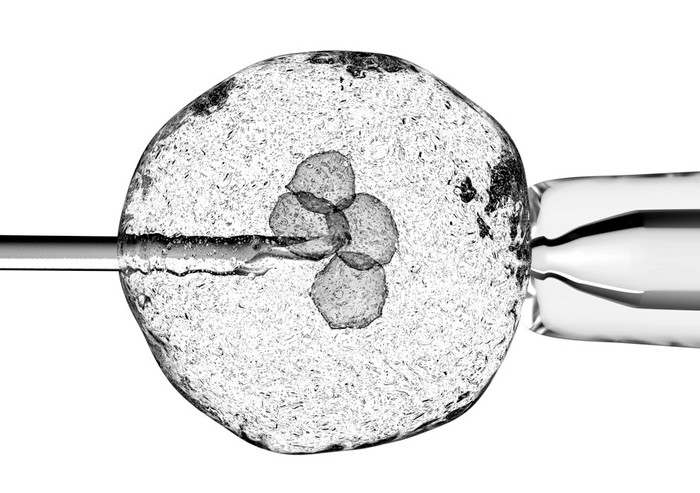

'키메라'라고도 알려진 인간-동물 잡종은 인간과 동물 세포가 혼합된 생물입니다. 그들은 인간 줄기 세포를 다른 동물의 배아에 주입하여 만듭니다. 지금까지 어떤 인간-동물 잡종 배아도 만삭에 이르지 못했습니다('만기'는 완전한 임신 기간을 의미합니다).

- 인간 유도 만능 줄기(iPS) 세포는 장기 수용자로부터 배아에 주입됩니다. 이 iPS 세포는 거의 모든 다른 세포로 발달할 수 있습니다.

- iPS 세포는 배아의 유전자가 남긴 공백을 채우고 수용자의 유전자로 인간의 장기를 만듭니다.